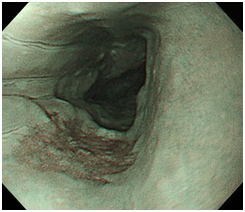

一般的には胃カメラと呼ばれている胃内視鏡検査は、口あるいは鼻から細長いスコープを入れて食道、胃、十二指腸などを直接観察できます。そのため微小な病変も見つけやすく、高精度な検査です。現在、胃がんは女性ではがん死亡原因の第4位、男性では第2位となっていますが、定期的に内視鏡検査を受けることで、早期発見、早期治療も可能になります。症状がなくても定期検査はとても大切です。